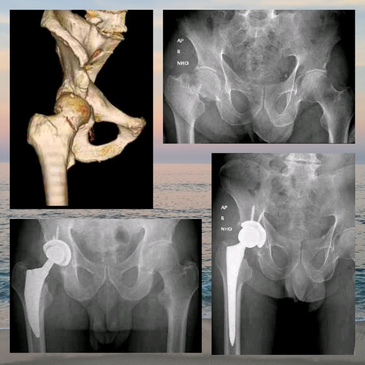

Dr. Rodrigo Aguirre Rojas is the best Orthopedic Surgeon in San Jose del Cabo, Mexico. Book your consultation for Hip and Knee Replacements in Los Cabos, Mexico at PlacidWay. Emergencies like Fractures and Dislocations are also evaluated and treated